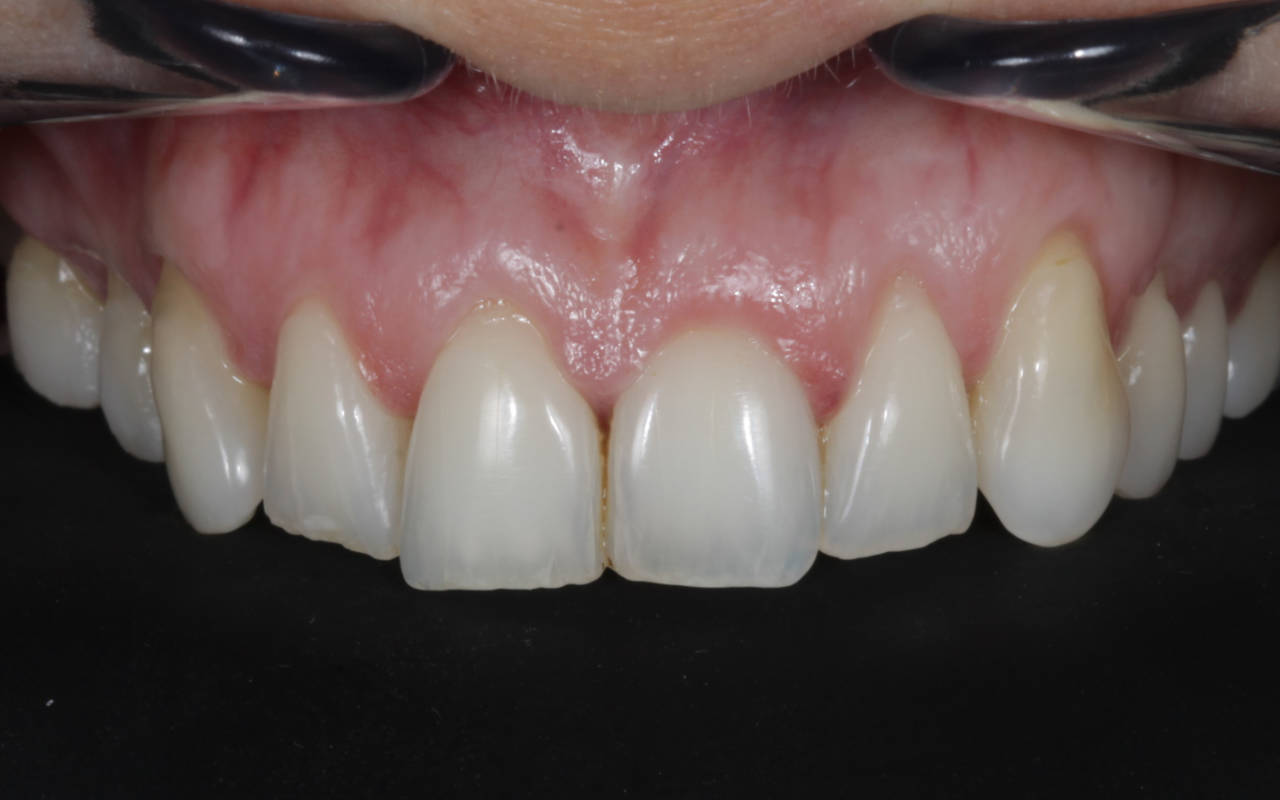

A harmonização do sorriso fez toda a diferença nes